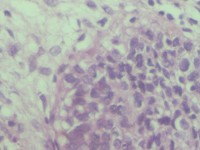

宫颈活检组织

性别

女

年龄

43岁

临床诊断

宫颈病变

一般病史

宫颈癌筛查:hpv16(+))

标本名称

宫颈组织

大体所见

灰白色组织

老师们看看,高级别累腺吗